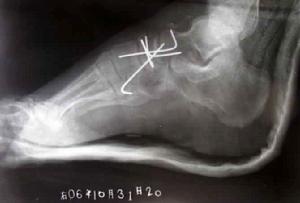

舟狀骨骨折在外展位平片上顯示為骨皮質不連續或骨周圍見細小的碎骨片影。要求拍攝外展位平片時,患者的掌骨一定要外展充分,當患者掌骨外展困難時拇側可稍做抬高,以求良好顯示舟狀骨。一般需同時拍攝健側平片,以便對照。有時也可做動態透視下點片,這都有利於提高檢出率。